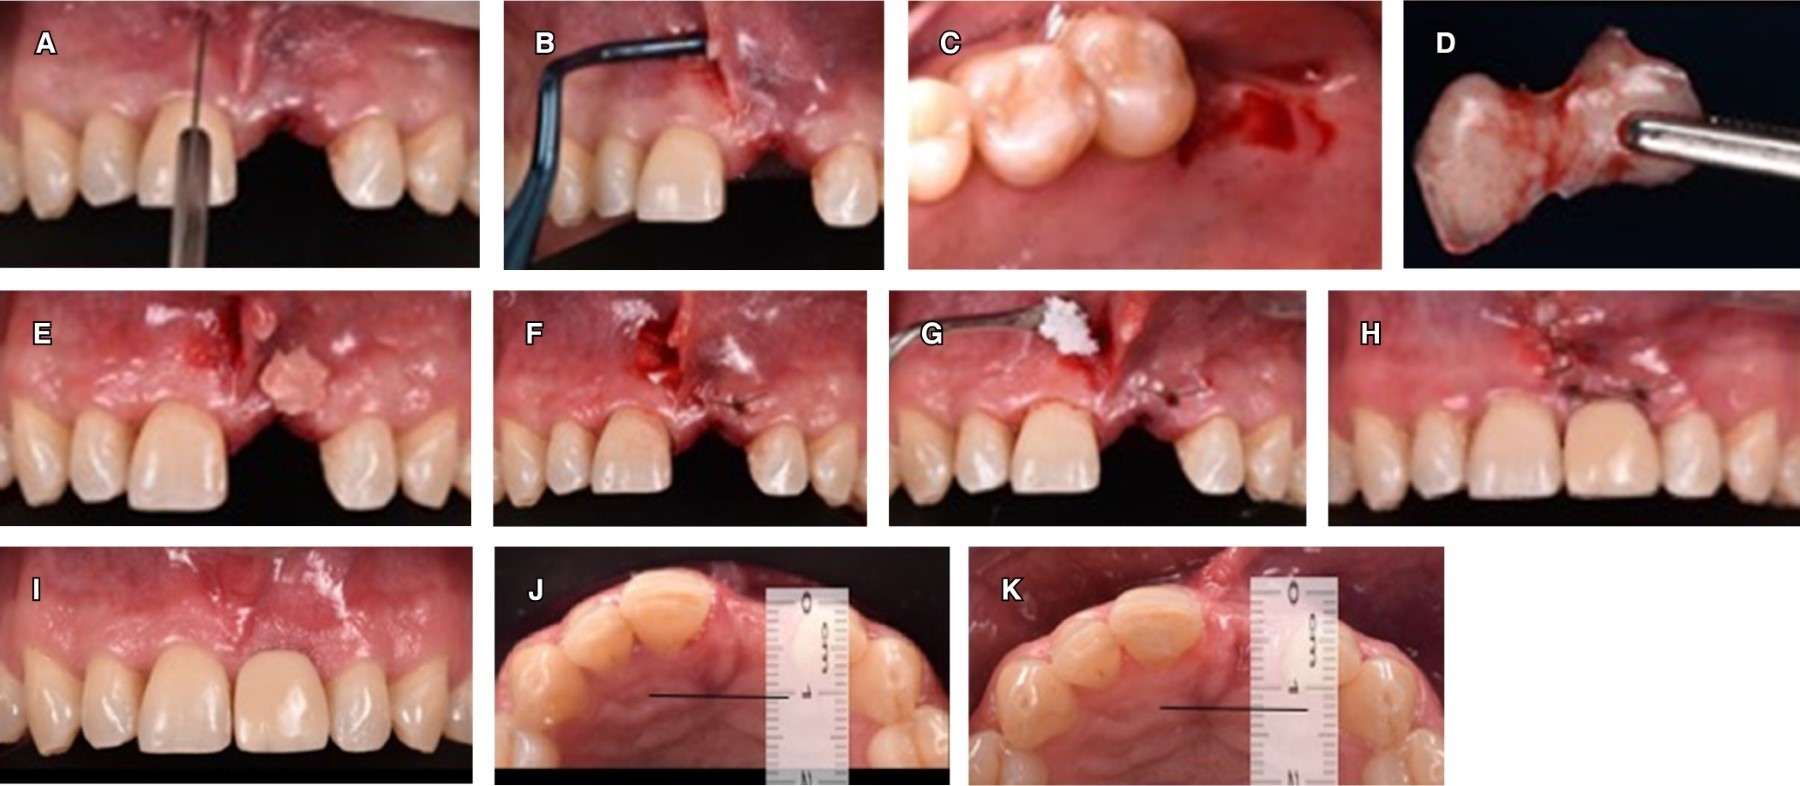

After implant placement, connective tissue and bone grafts were used to prepare the receptor site with the VISTA tunneling technique because it is a minimally invasive technique. It avoids flap elevation and preserves the blood supply to prevent bone tissue collapse and loss of the interdental papilla thus providing greater postoperative comfort for the patient. A vertical incision was made adjacent to the labial frenulum (Figure 7A-C); guided bone regeneration was performed through a tunnel, using connective tissue graft (Figure 7D-E). The donor site was the retromolar area of the maxilla, distal to molar 17; xenograft (NuOss) was placed (Figure 6F-G) in addition to resorbable collagen membrane (RCM6) and it was sutured with 5-0 catgut thread (Figure 7H). A provisional prosthesis was attached with orthodontic wire to the adjacent teeth (Figure 7I). Figure 7J depicts the pre-surgical situation; after 3 months of healing, an increase in height of the gingival margin that outlines tooth 21 was obtained, around 0.5 mm (Figure 7K).

An esthetic, biological and functional restoration was achieved, in addition to an increase in the horizontal ridge (2 mm) (Figure 7J) which offers better stability in the implant support tissues, and mimicry of the implant-supported restoration with the rest of the mouth (Figure 8).

Figure 7